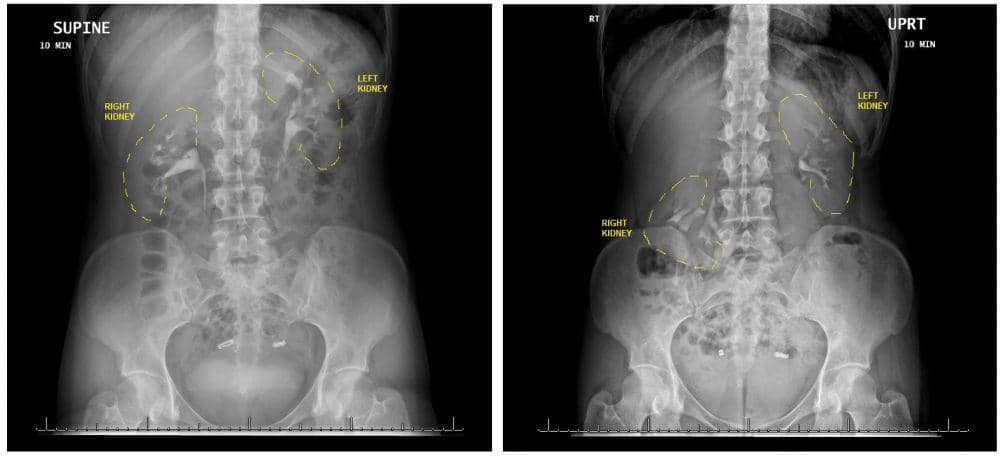

Nefroptosis paling baik didiagnosis dengan serangkaian studi pencitraan yang menciptakan apa yang dikenal sebagai urogram. Jika dokter mencurigai nefroptosis adalah penyebab gejala, dokter kemungkinan akan melakukan tes dengan pewarna yang ditambahkan ke aliran darah untuk membantu melihat ginjal.

Tes harus dilakukan ketika orang tersebut berbaring dan berdiri. Lewat gambar, seseorang dengan nefroptosis akan dengan jelas menunjukkan ginjal turun sekitar 5 cm.